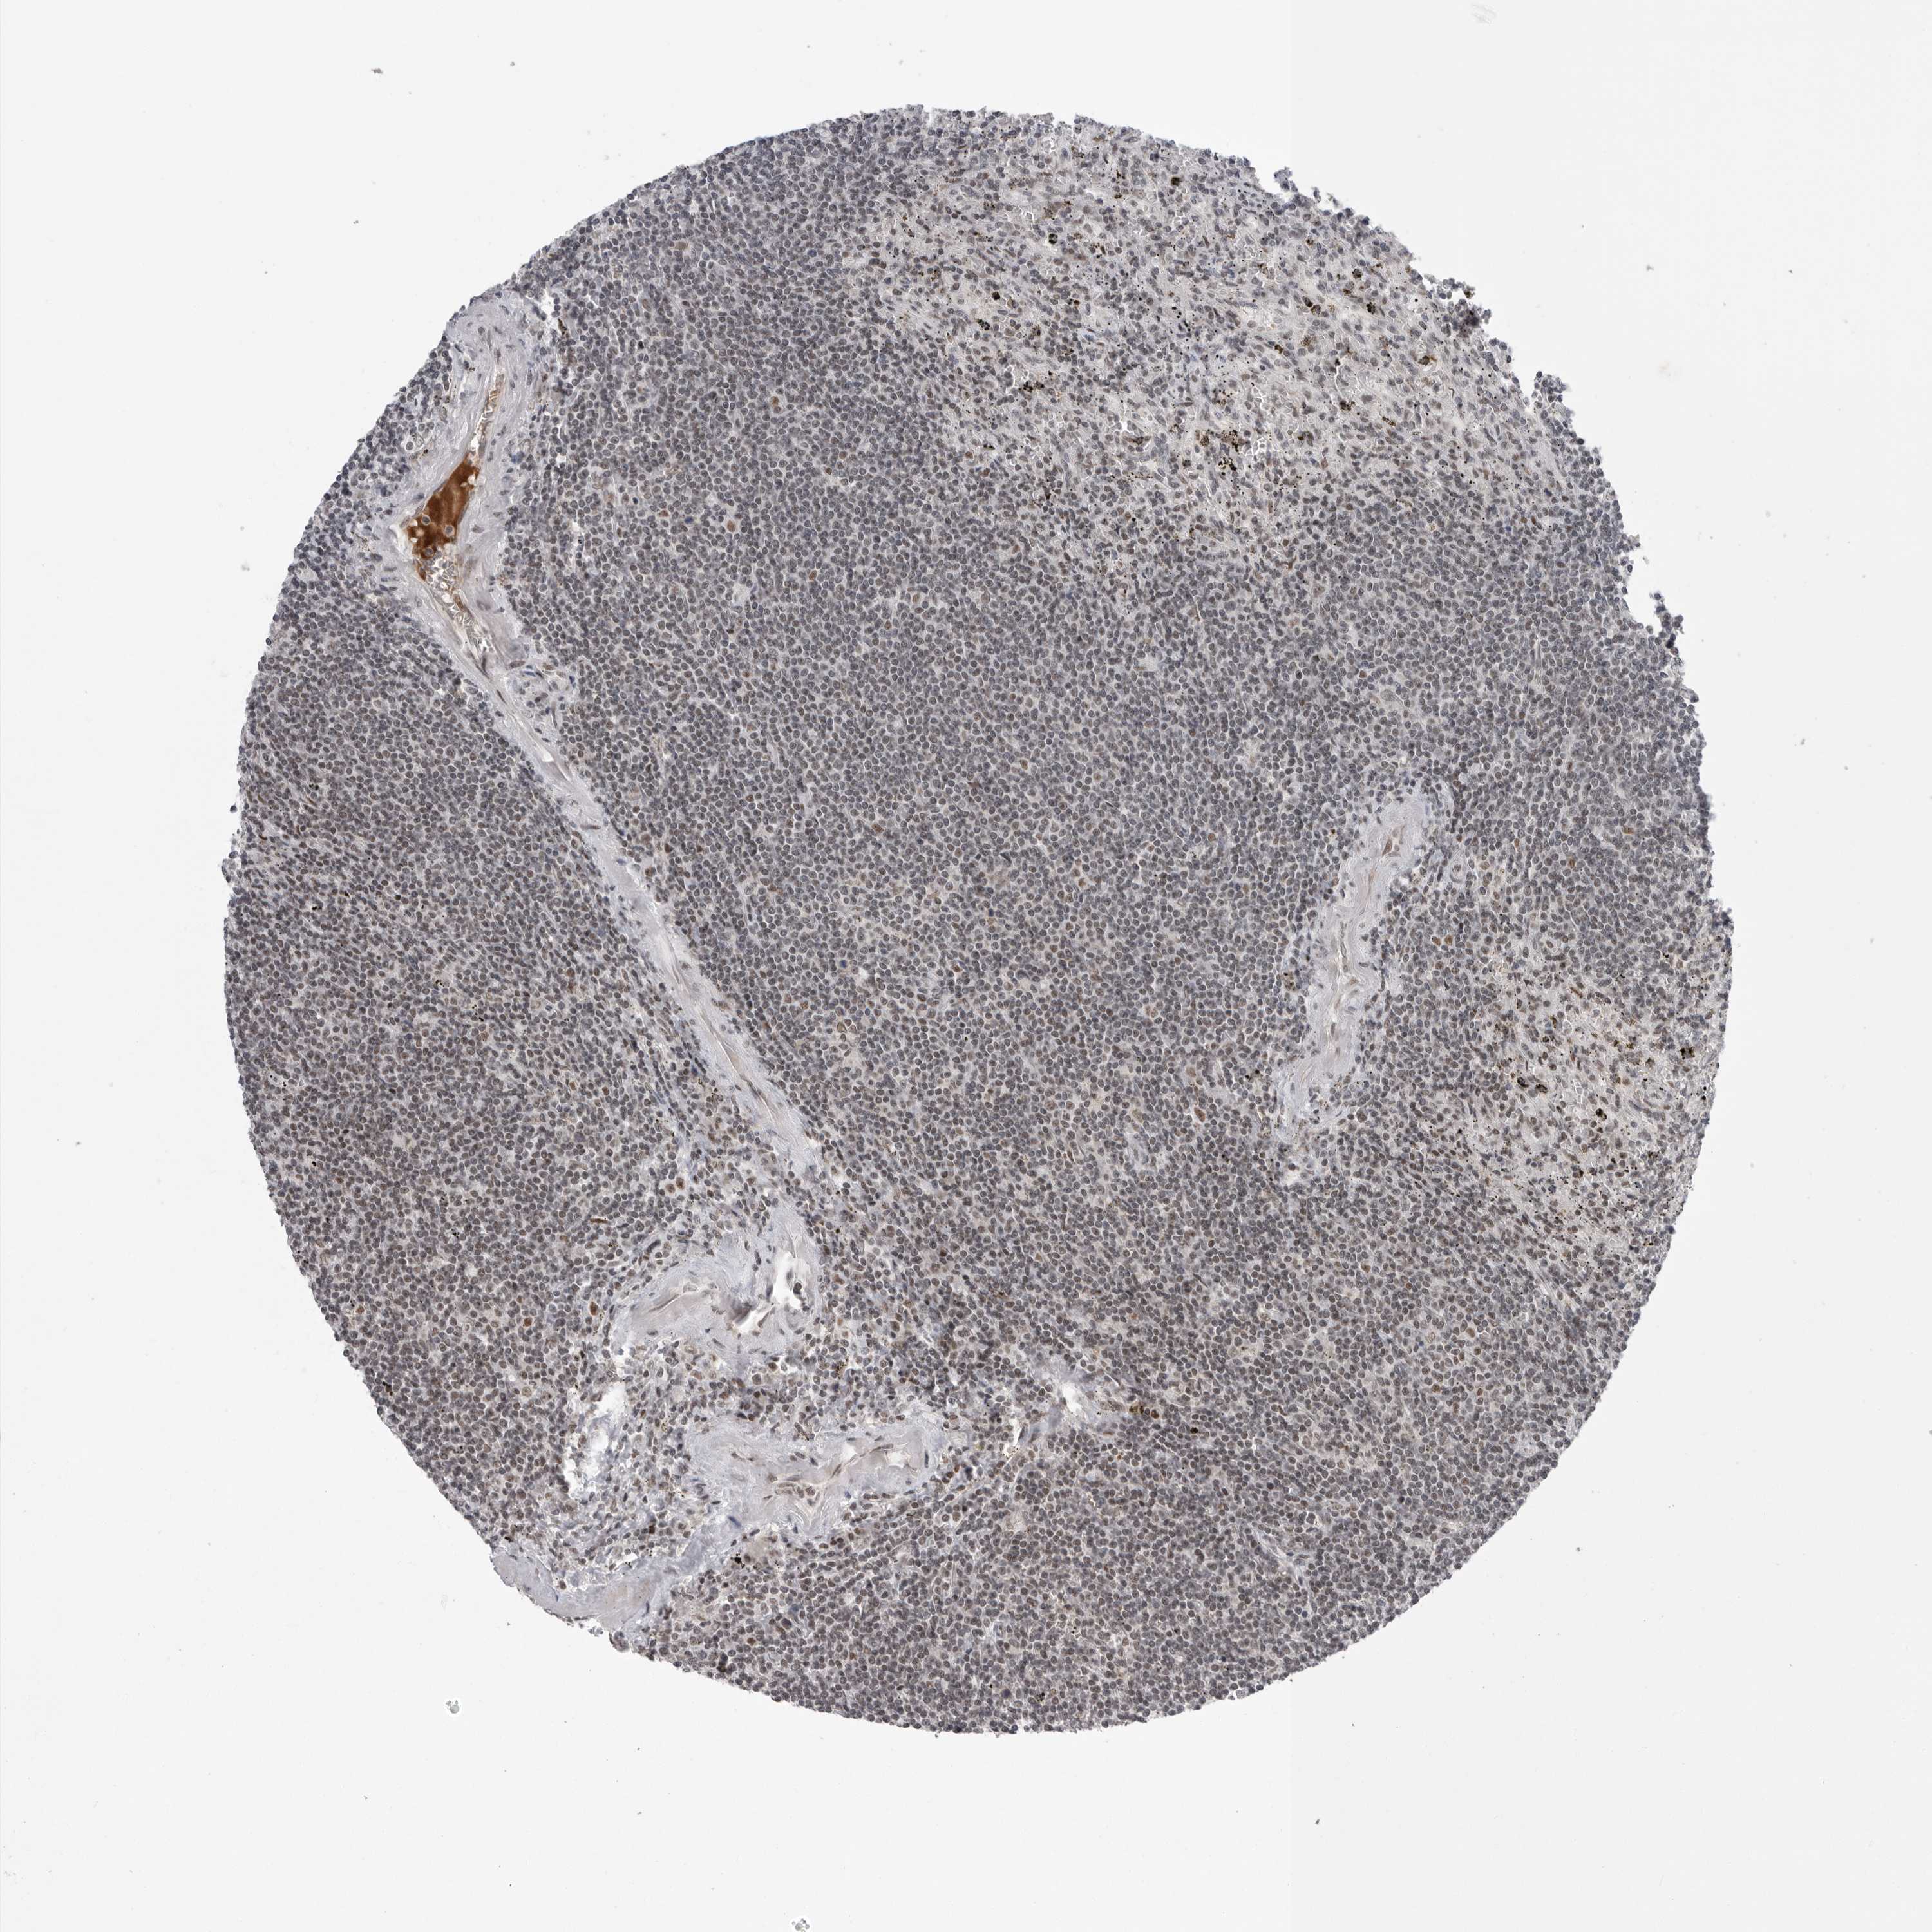

CANCER LYMPHOMA Show tissue menu

LYMPHOMA - Protein expressioni

A mouse-over function shows sample information and annotation data. Click on an image to view it in a full screen mode. Samples can be filtered based on level of antibody staining by selecting one or several of the following categories: high, medium, low and not detected. The assay and annotation is described here.

Each image is clickable and will lead to virtual microscopy that enables deeper exploration of all samples and also displays staining intensity scores, fraction scores and subcellular localization as well as patient and tissue information for each sample.

Antibody CAB025600

Antibody CAB026380

Antibody CAB079773

Staining

High

Medium

Low

Not detected

Intensity

Strong

Moderate

Weak

Negative

Quantity

>75%

75%-25%

<25%

None

Location

Nuclear

Cytoplasmic/membranous

Cytoplasmic/membranous,nuclear

Hodgkin's disease, NOS

Malignant lymphoma, non-Hodgkin's type, Low grade

Malignant lymphoma, non-Hodgkin's type, High grade